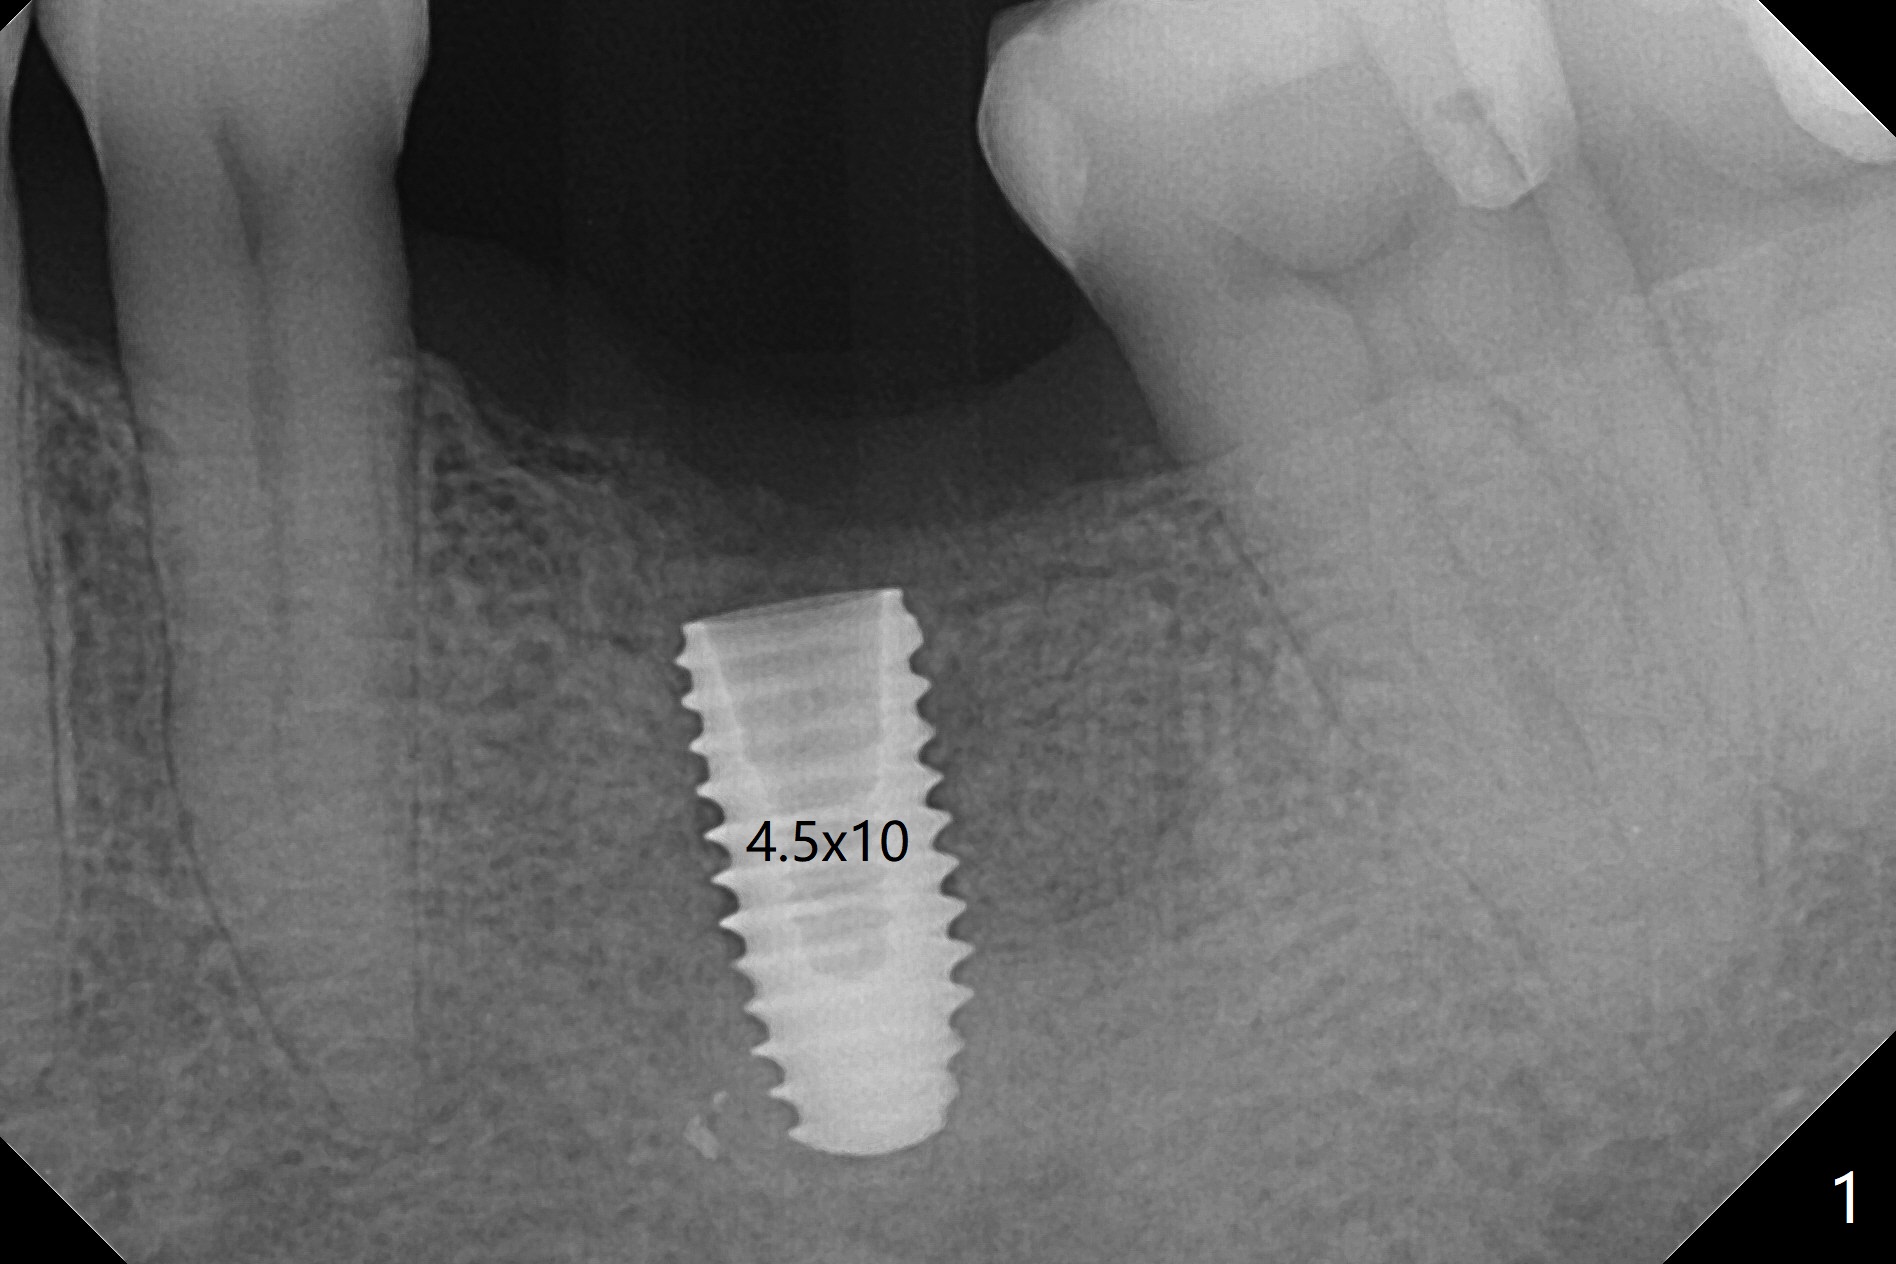

A 4.5x10 mm implant is well placed at #19 in term of trajectory with guide (Fig.1). Because of crestal bone resorption, the implant is placed deep with increased potential of abutment screw loosening. The key to prevention of bone loss is socket shield. A 6x5 mm healing abutment is placed with 10 Ncm (Fig.3 (PA taken 21 days postop)).